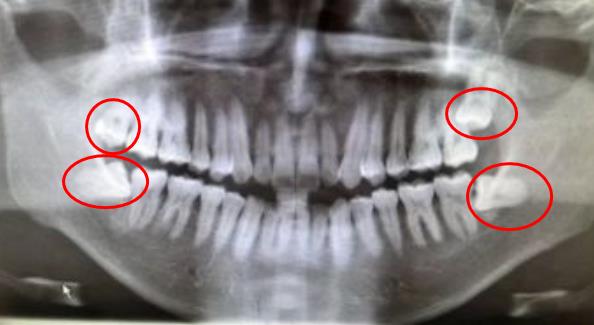

上下頜共有4顆智齒